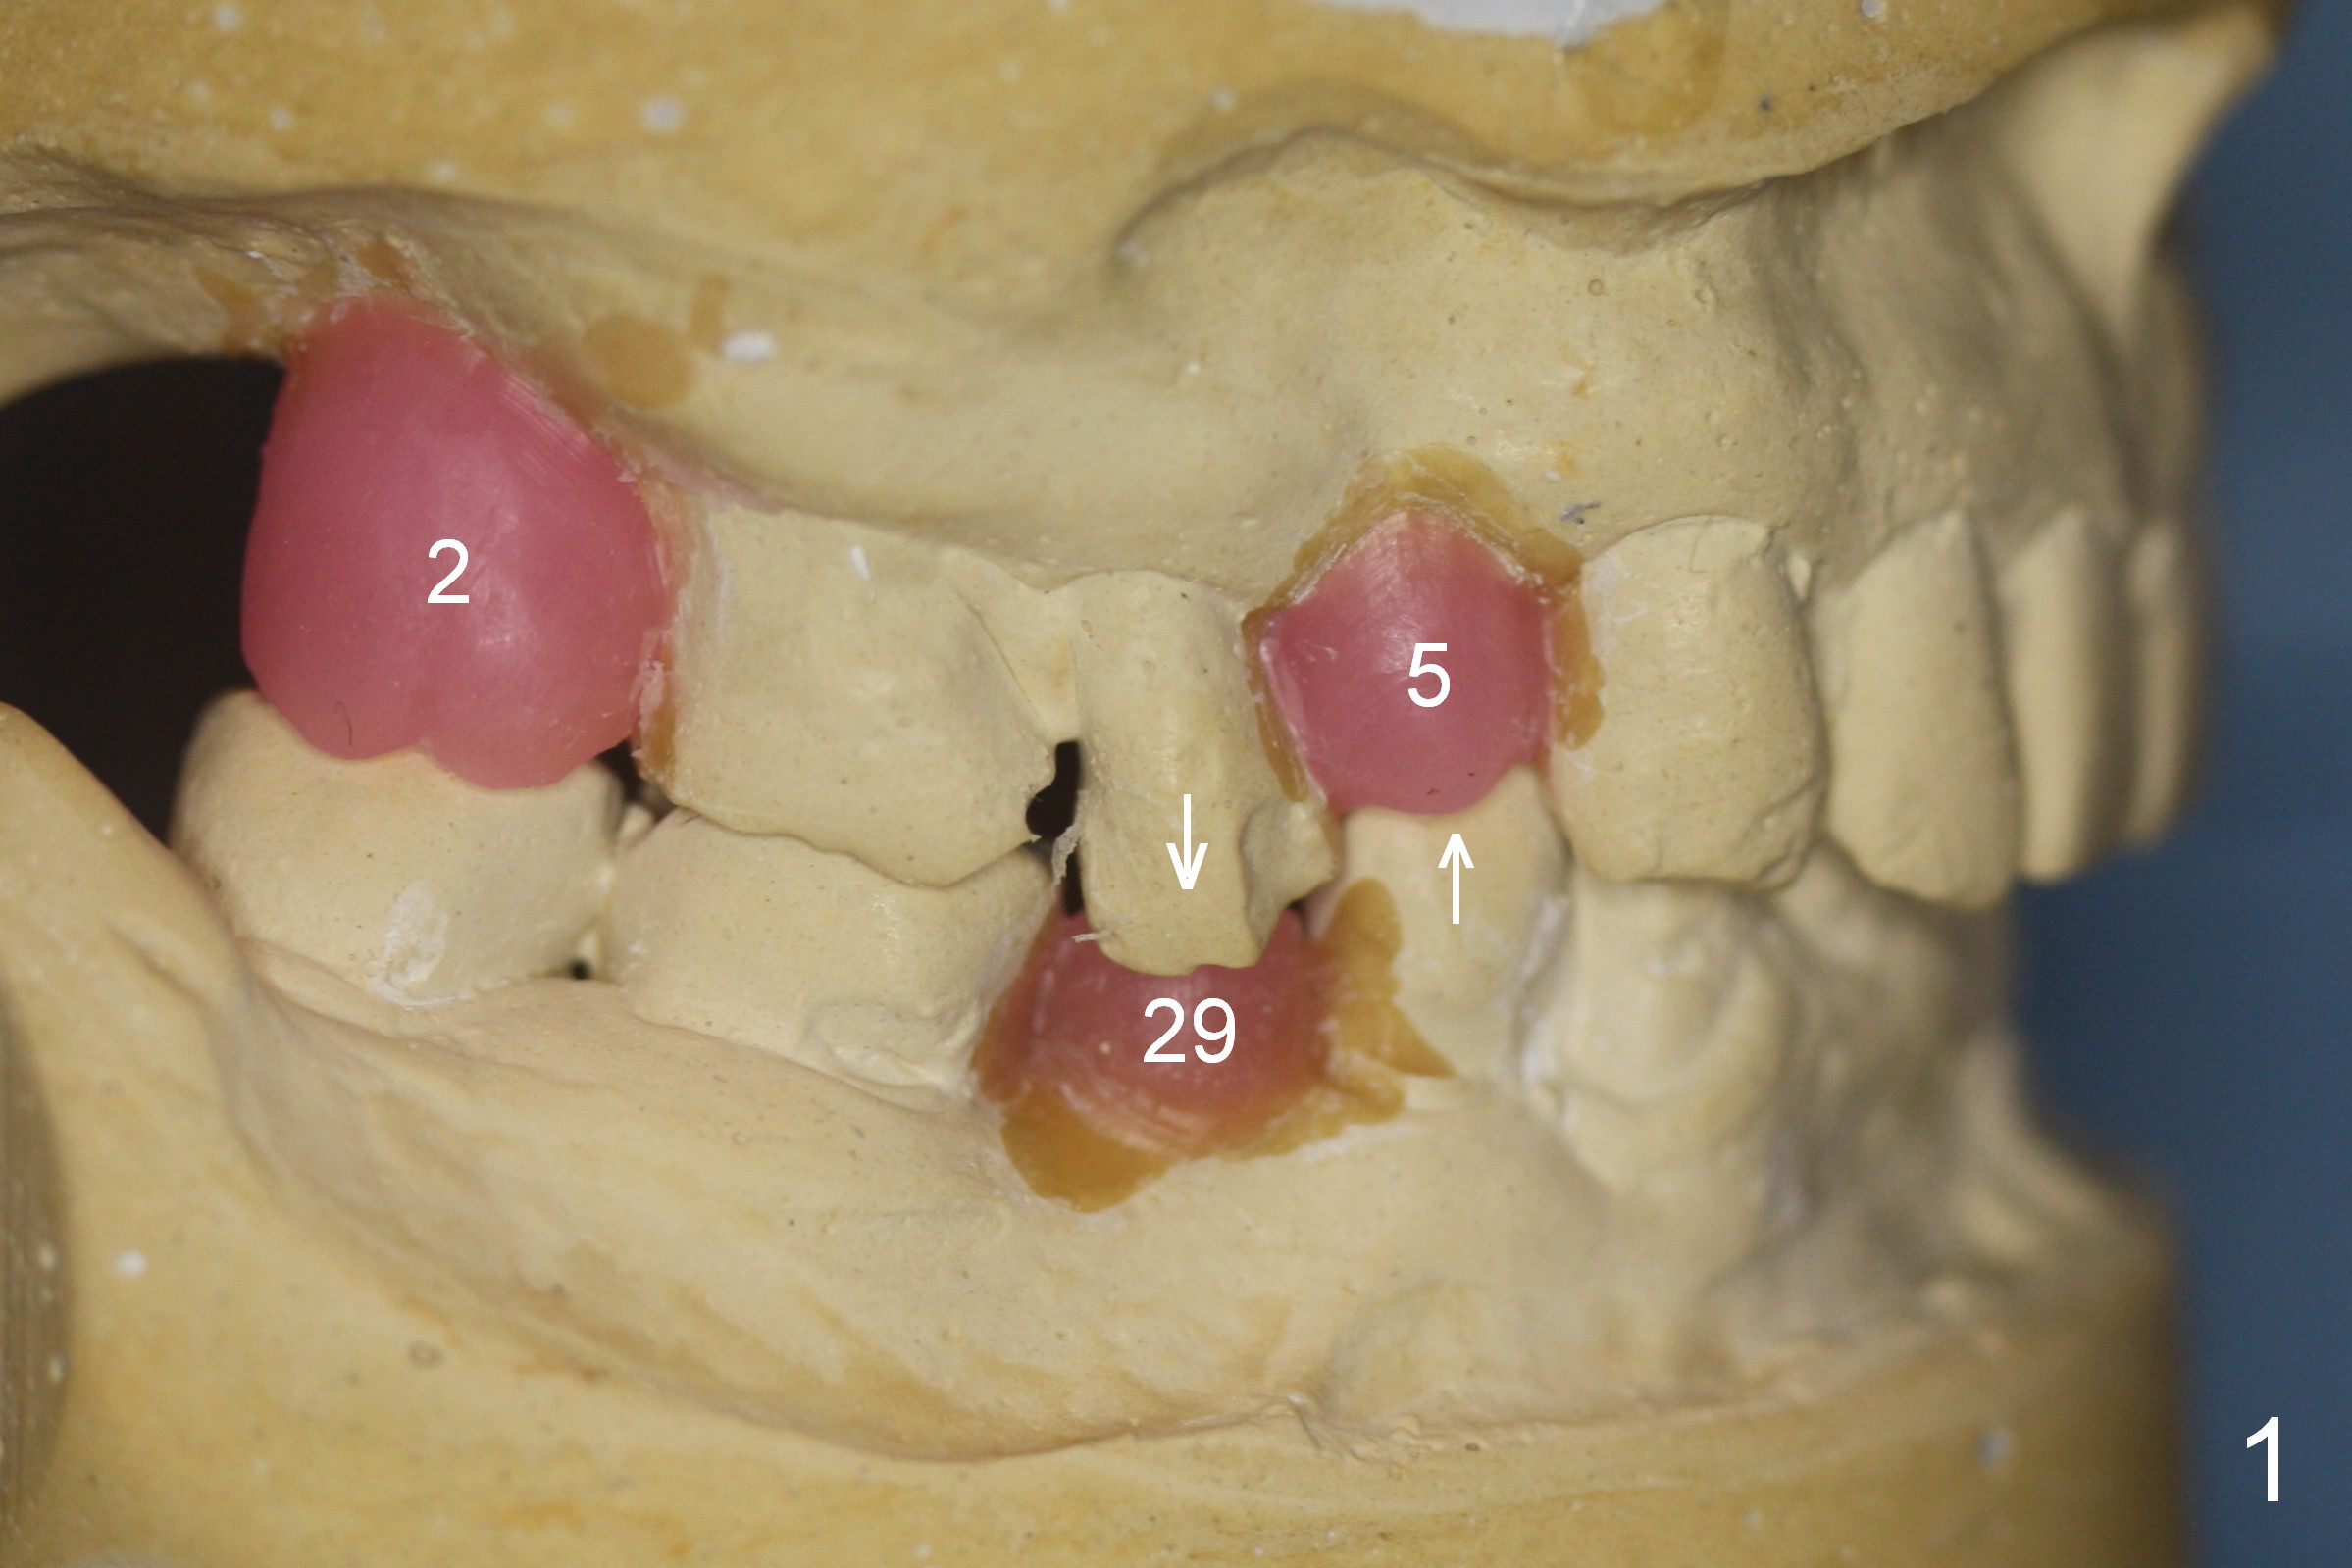

A 56-year-old man has long-termed partial edentulism (#2,5,14,15 (not shown),29, Fig.1). There is supraeruption of the opposing teeth (Fig.1 arrows). If an immediate provisional is provided, it should have plenty of clearance to avoid micromovement of the implant. Once the implants at #2,5, and 29 osteointegrate, they will be used as anchorage for intrusion (Fig.2,3 arrows, segmental orthodontics).

The first implant will be placed at #29 (Fig.4,5). The pointed ridge will be flattened to start osteotomy (Fig.6,7 (surgical handpiece)). The buccolingual dimension of the flattened ridge should be ~ 6 mm. The initial depth will be 12 mm. Take the 1st PA. A restorative high speed handpiece may be needed to remove the enamel of the mesial surface of #30 and the distal surface of #28 to increase space for implant placement.